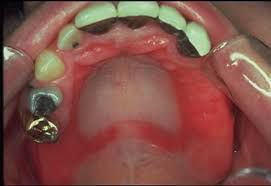

Denture stomatitis (DS) or thrush is a localized infection in the mouth caused by yeast or fungus. It is caused by a high concentration of microbes called candida. The infection is non-communicable and affects palatal and gingival mucosa. DS is also commonly called 'denture sore mouth' and 'prosthetic stomatitis. '